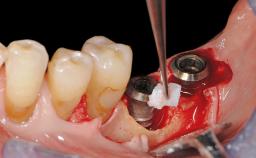

Late Presentation of Peri-Implant Mucositis Requiring Soft-Tissue Augmentation and Esthetic Crown Lengthening at Implant Site 11

Eduardo R Lorenzana, Jason R Gillespie

Biological or technical complications around implant-supported prostheses place a significant burden on patients as well as the surgical and restorative team. Inflammation of the peri-implant soft tissues is often the first sign that something has gone awry. While there is never a good time for a complication, late presentation of inflammation in the soft tissues around a long-standing prosthesis triggers a period of research and review of the case in order to ascertain the treatment history and its possible contribution to the etiology of the situation. This becomes more complicated in situations where a patient has not received regular maintenance and clinical/radiographical examinations due to personal, financial, or professional reasons. When the complication occurs in the esthetic zone, the complexity of the situation expands exponentially, as the only acceptable outcome in the patient’s eyes will be the maintenance of the esthetics of the prosthesis.